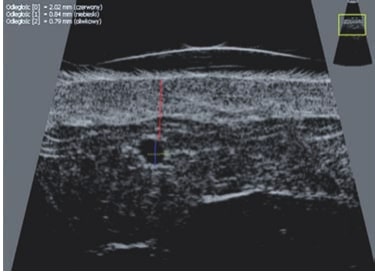

Für die vorliegende Arbeit wurden Ultraschallaufnahmen mit Hochfrequenzgeräten erstellt, nämlich Episcan mit mechanischer Sonde 50 MHz (Longport International, Großbritannien, USA), DermaMed mit mechanischer Sonde 48 MHz (Dramiński, Polen), Sonix mit elektronischer Lineararray-Sonde 40 MHz (Ultrasonix, Kanada).

Die Doppler-Sonographie ermöglicht die Darstellung großer Gefäße und Perforatoren, die sich meist in tieferen Bereichen des subkutanen Gewebes befinden. Mit klassischem Ultraschall lassen sich kleinere Gefäße jedoch nicht darstellen. Für die Darstellung kleinerer Gefäße, die oberflächlich unter der Epidermis und im oberen subkutanen Gewebe liegen, wird HFU eingesetzt. Mit Sonden über 20 MHz Frequenz erhält man hochauflösende Ultraschallbilder, auf denen Objekte kleiner als 0,1 mm unterscheidbar sind. Mit zunehmender Auflösung nimmt jedoch die Eindringtiefe ab. Je nach Sonde und Gerät beträgt die maximale Eindringtiefe etwa 20–30 mm. Diese Eindringtiefe bei gleichzeitig hoher Bildauflösung ermöglicht die Beurteilung sehr kleiner Gefäße. HFU erlaubt die genaue Bestimmung des Verlaufs und der Lage kleiner Gefäße in der Haut, was entscheidend für die Wahl der Verschlussmethode und die Planung des Eingriffs ist. Oft sind an der Hautoberfläche nur wenige Gefäße sichtbar – erst durch die Ultraschalluntersuchung lässt sich die tatsächliche Anzahl und der Verlauf feststellen. Für einen erfolgreichen Verschluss muss das gesamte Gefäß behandelt werden, nicht nur der sichtbare Teil, da sonst eine schnelle Rekanalisation erfolgt (7). Häufig ändert das an der Haut sichtbare Gefäß seinen Verlauf, wird gewundener und zieht in tiefere Hautschichten (8). HFU ermöglicht zudem die Darstellung der Perforatoren zwischen kleinen Gefäßen und die Messung grundlegender Parameter wie Durchmesser, Wandstärke, Tiefe und Blutfluss (6). Mit der 40-MHz-Sonde von Ultrasonix kann auch der Blutfluss mittels Farbdoppler visualisiert werden.